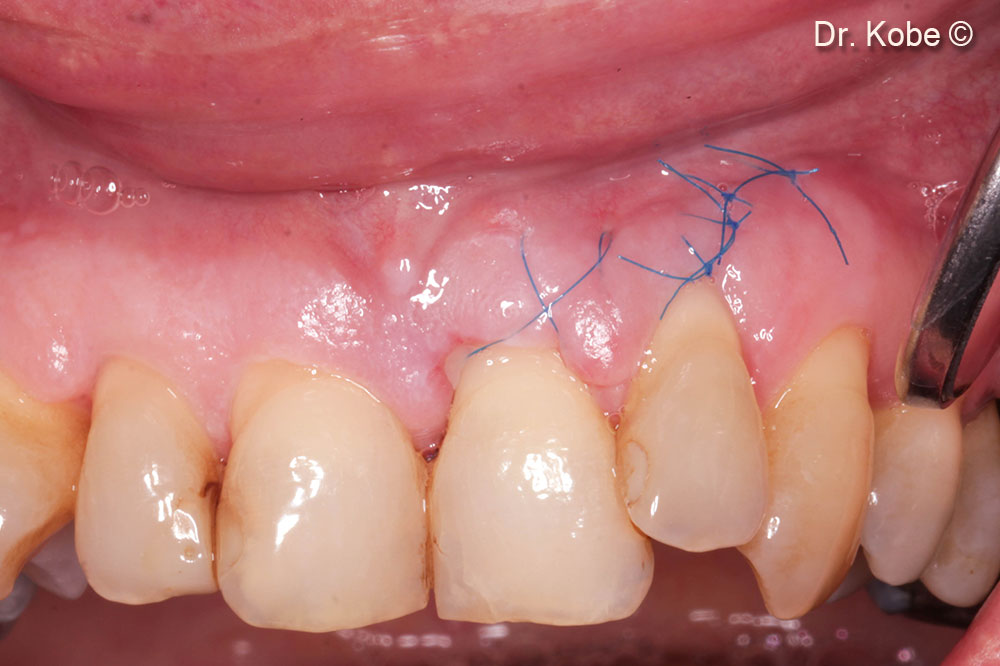

7. Wound sutured with interrupted sutures

8. Complete wound closure after 1 week